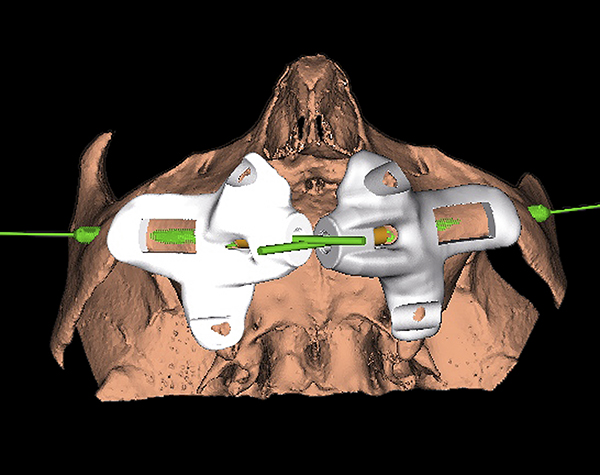

Computer-Guided Approach for Placement of Zygomatic Implants